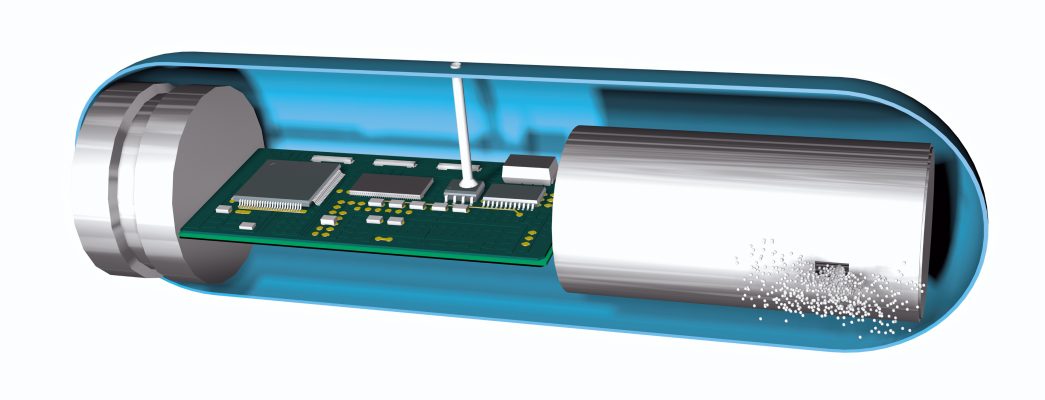

Thanks to highly miniaturised PCB technology as a carrier for the corresponding electronics, ‘smart capsules’, which monitor specific body parameters and transmit the relevant data or deliver a controlled dose of medication, are now a reality too.